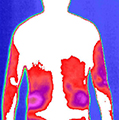

治疗前后炎症对比图/ Inflammation contrast

• 治疗前